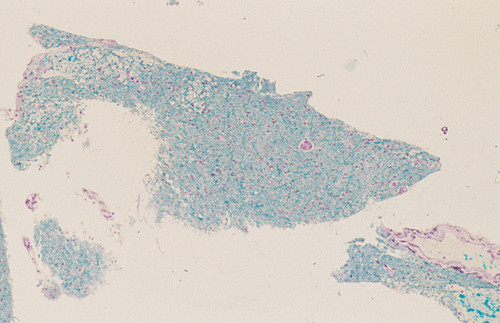

LFB/PAS

Streotactic biopsy yielded several cores of tissue. On scanning magnification, there are multiple small lymphocytic collections (Ž in Panel C) in the white matter. On higher magnification, these areas contain mostly lymphocytes without atypia. These collections appear to be angiocentric and are often admixed with some foamy macrophages (Panel  D and E). On LFB/PAS stain, multiple small, irregular areas of angiocentric pale staining are present (Panel F and G). On high magnification, these areas are featured by infiltration by foamy macrophages and lymphocytes and myelin loss (Panel  H). On Bielschowsky stain, the axons in these pale areas are largely preserved. Immunohistochemistry on GFAP demonstrates multiple stellate reactive astrocytes (Panel J). The macrophages and lymphocytes are also well demonstrated by immunohistochemistry for CD68 and LCA respectively (Panel  K and L).

The histopathology of inflammatory demyelinating pseudotumors is very similar to that of acute disseminated perivsnous encephalomyelitis or the classic type of ADEM. In essence, there is perivenous chronic inflammatory cell infiltration accompanied by infiltrating, foamy macrophages with an angiocentric distribution. Loss of myelin and relative preservation of axon fibers must be demonstrated before a diagnosis of demyelinating process is made. The loss of myelin can be well demonstrated by special stains for myelin with the Luxol fast blue based stains as one of the most commonly used stains. Relative preservation of axons can be sell demonstrated by silver stains such as Bodian stain, Bielschowsky stain, and also immunohistochemistry for moderate and high molecular weight neurofilament proteins. The pathologic highlights on separating inflammatory demyelinating lesions from mimicking lesions have been well described by Zagzag et al. 8. Other inflammatory lesions, particularly viral infectons, must also be ruled out. Keen observations particularly for nuclear inclusion bodies, immunohistochemistry for specific viral agents, and laboratory studies of the cerebral spinal fluid (CSF) and blood are often helpful. Identification of oligoclonal bands on electrophoresis of CSF is a strong suggesting of a demyelinating process.